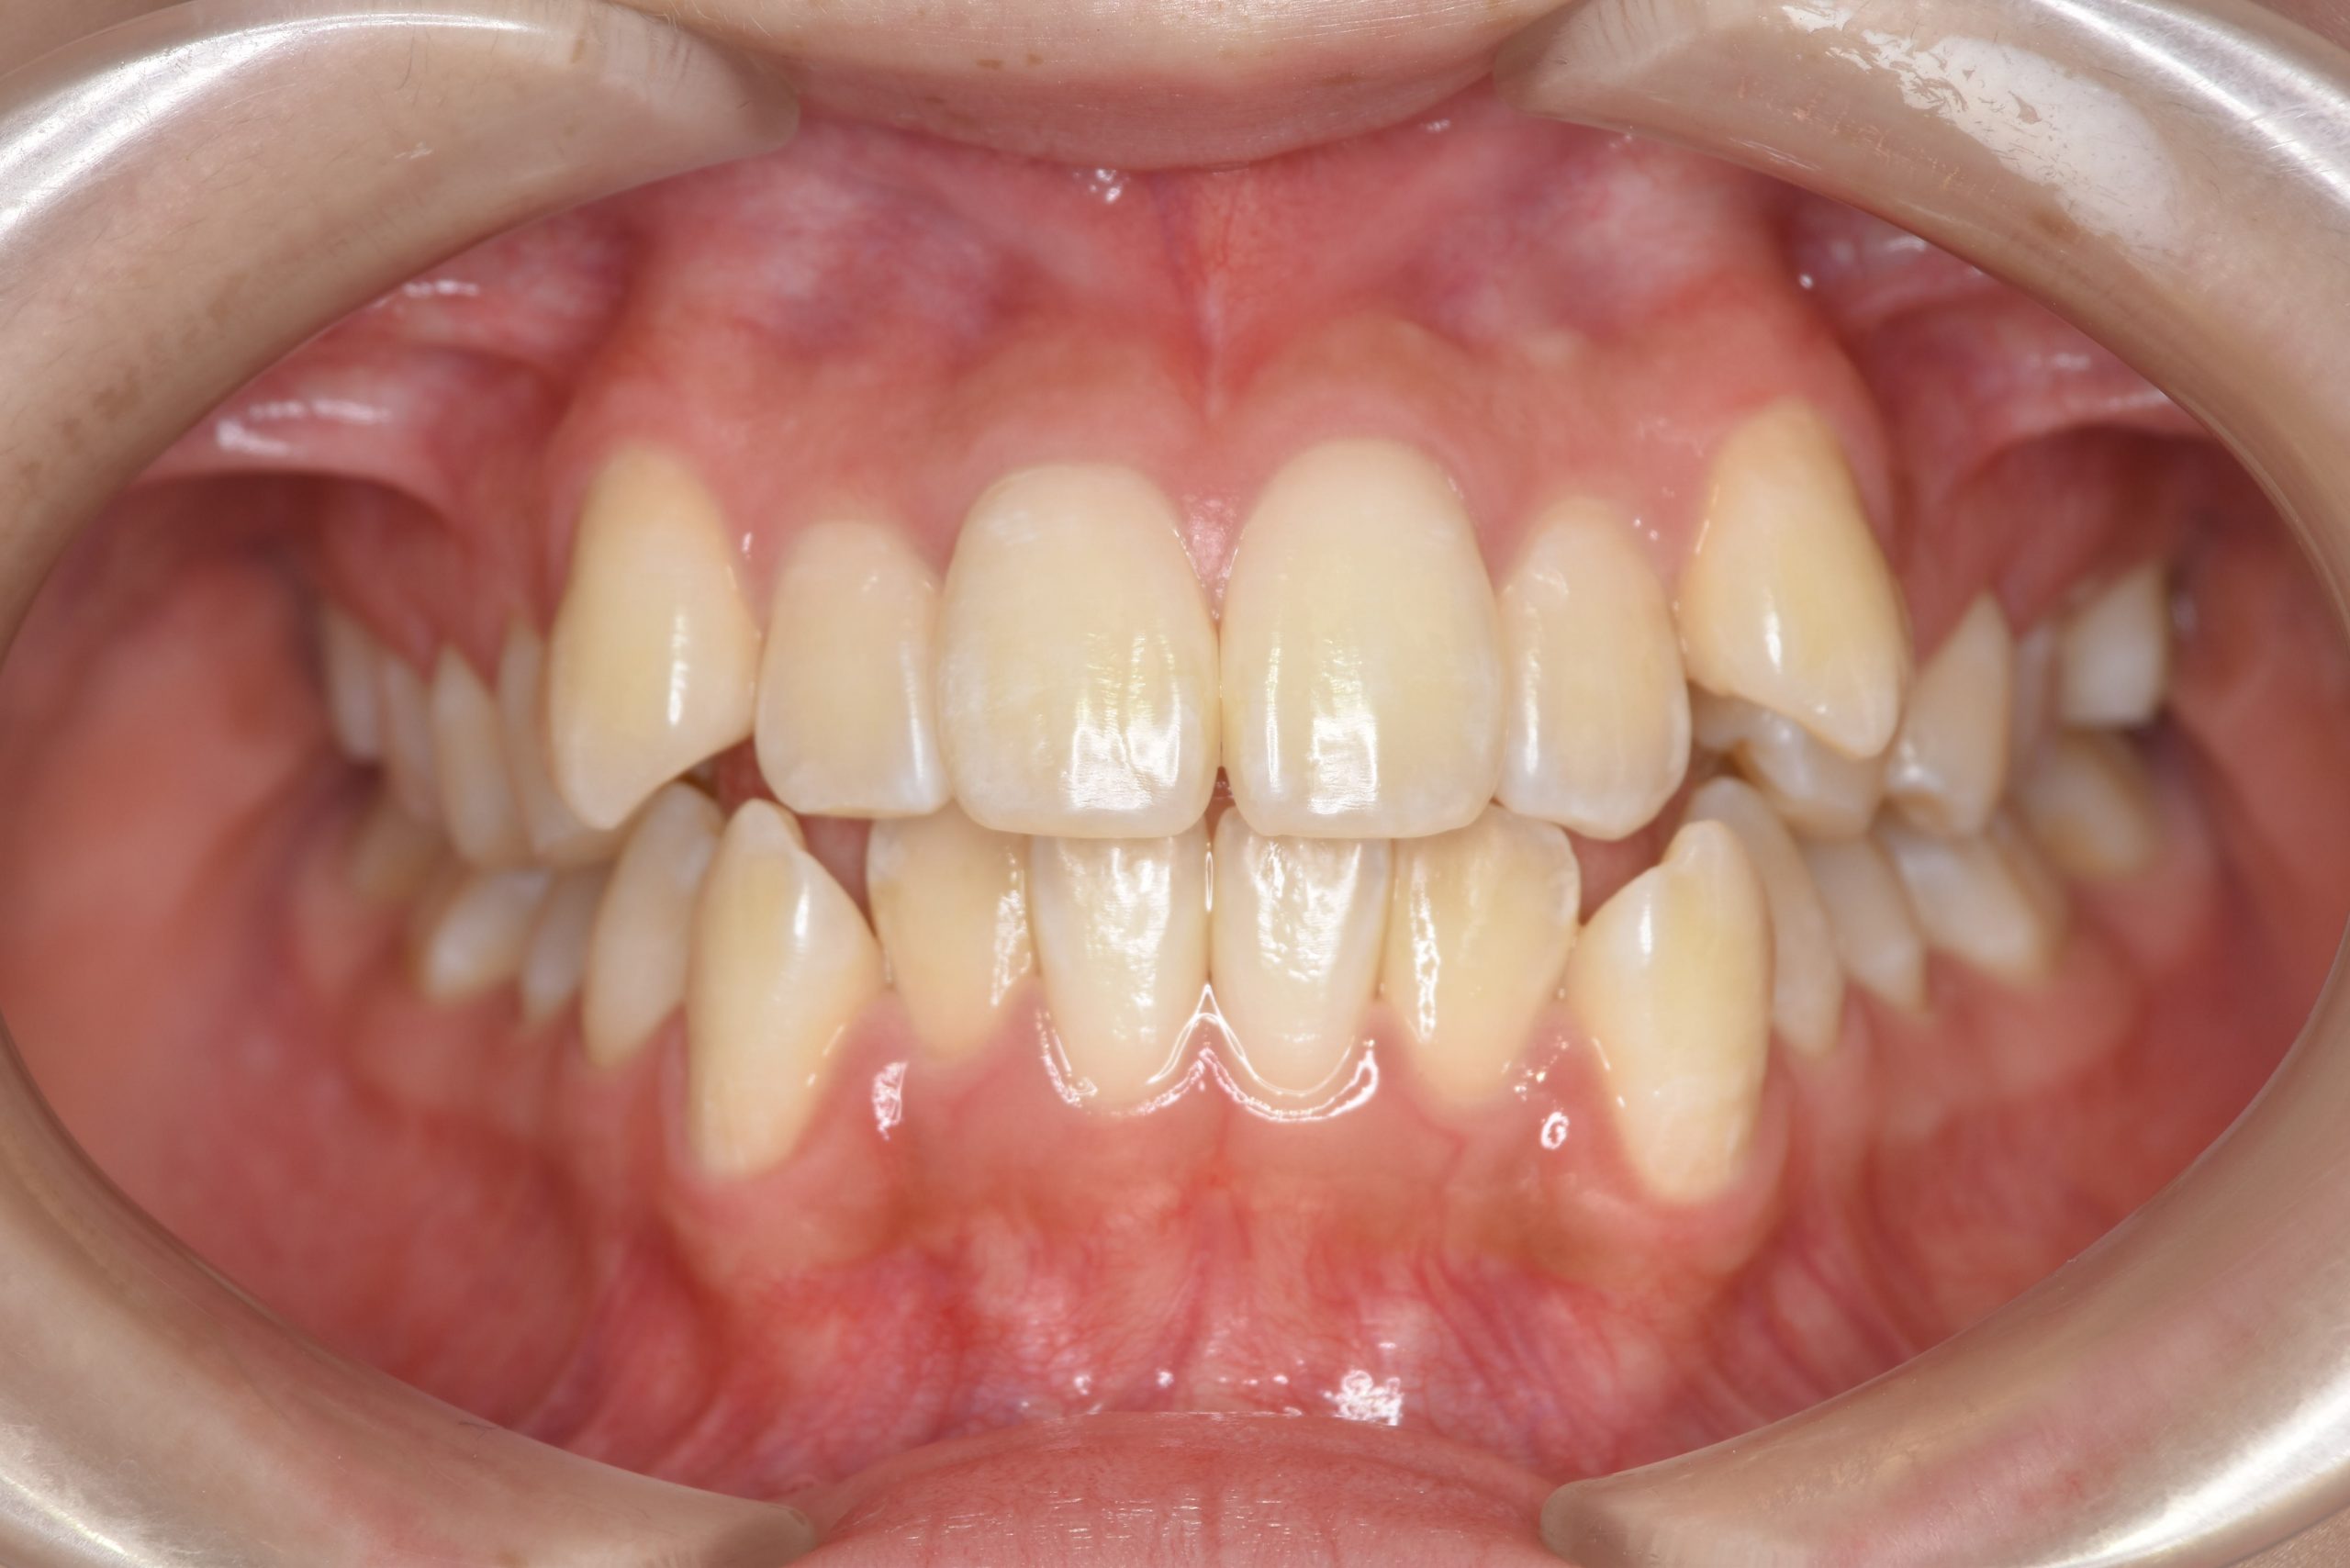

ビフォー

全顎ワイヤー矯正 症例_815

アフター

主訴 前歯の出っ歯|八重歯|下の歯のデコボコ|検診で噛み合わせが悪いと指摘されたこと

施術内容 成人矯正1期治療

治癒期間 1年4か月間

費用 954,800円(税込)